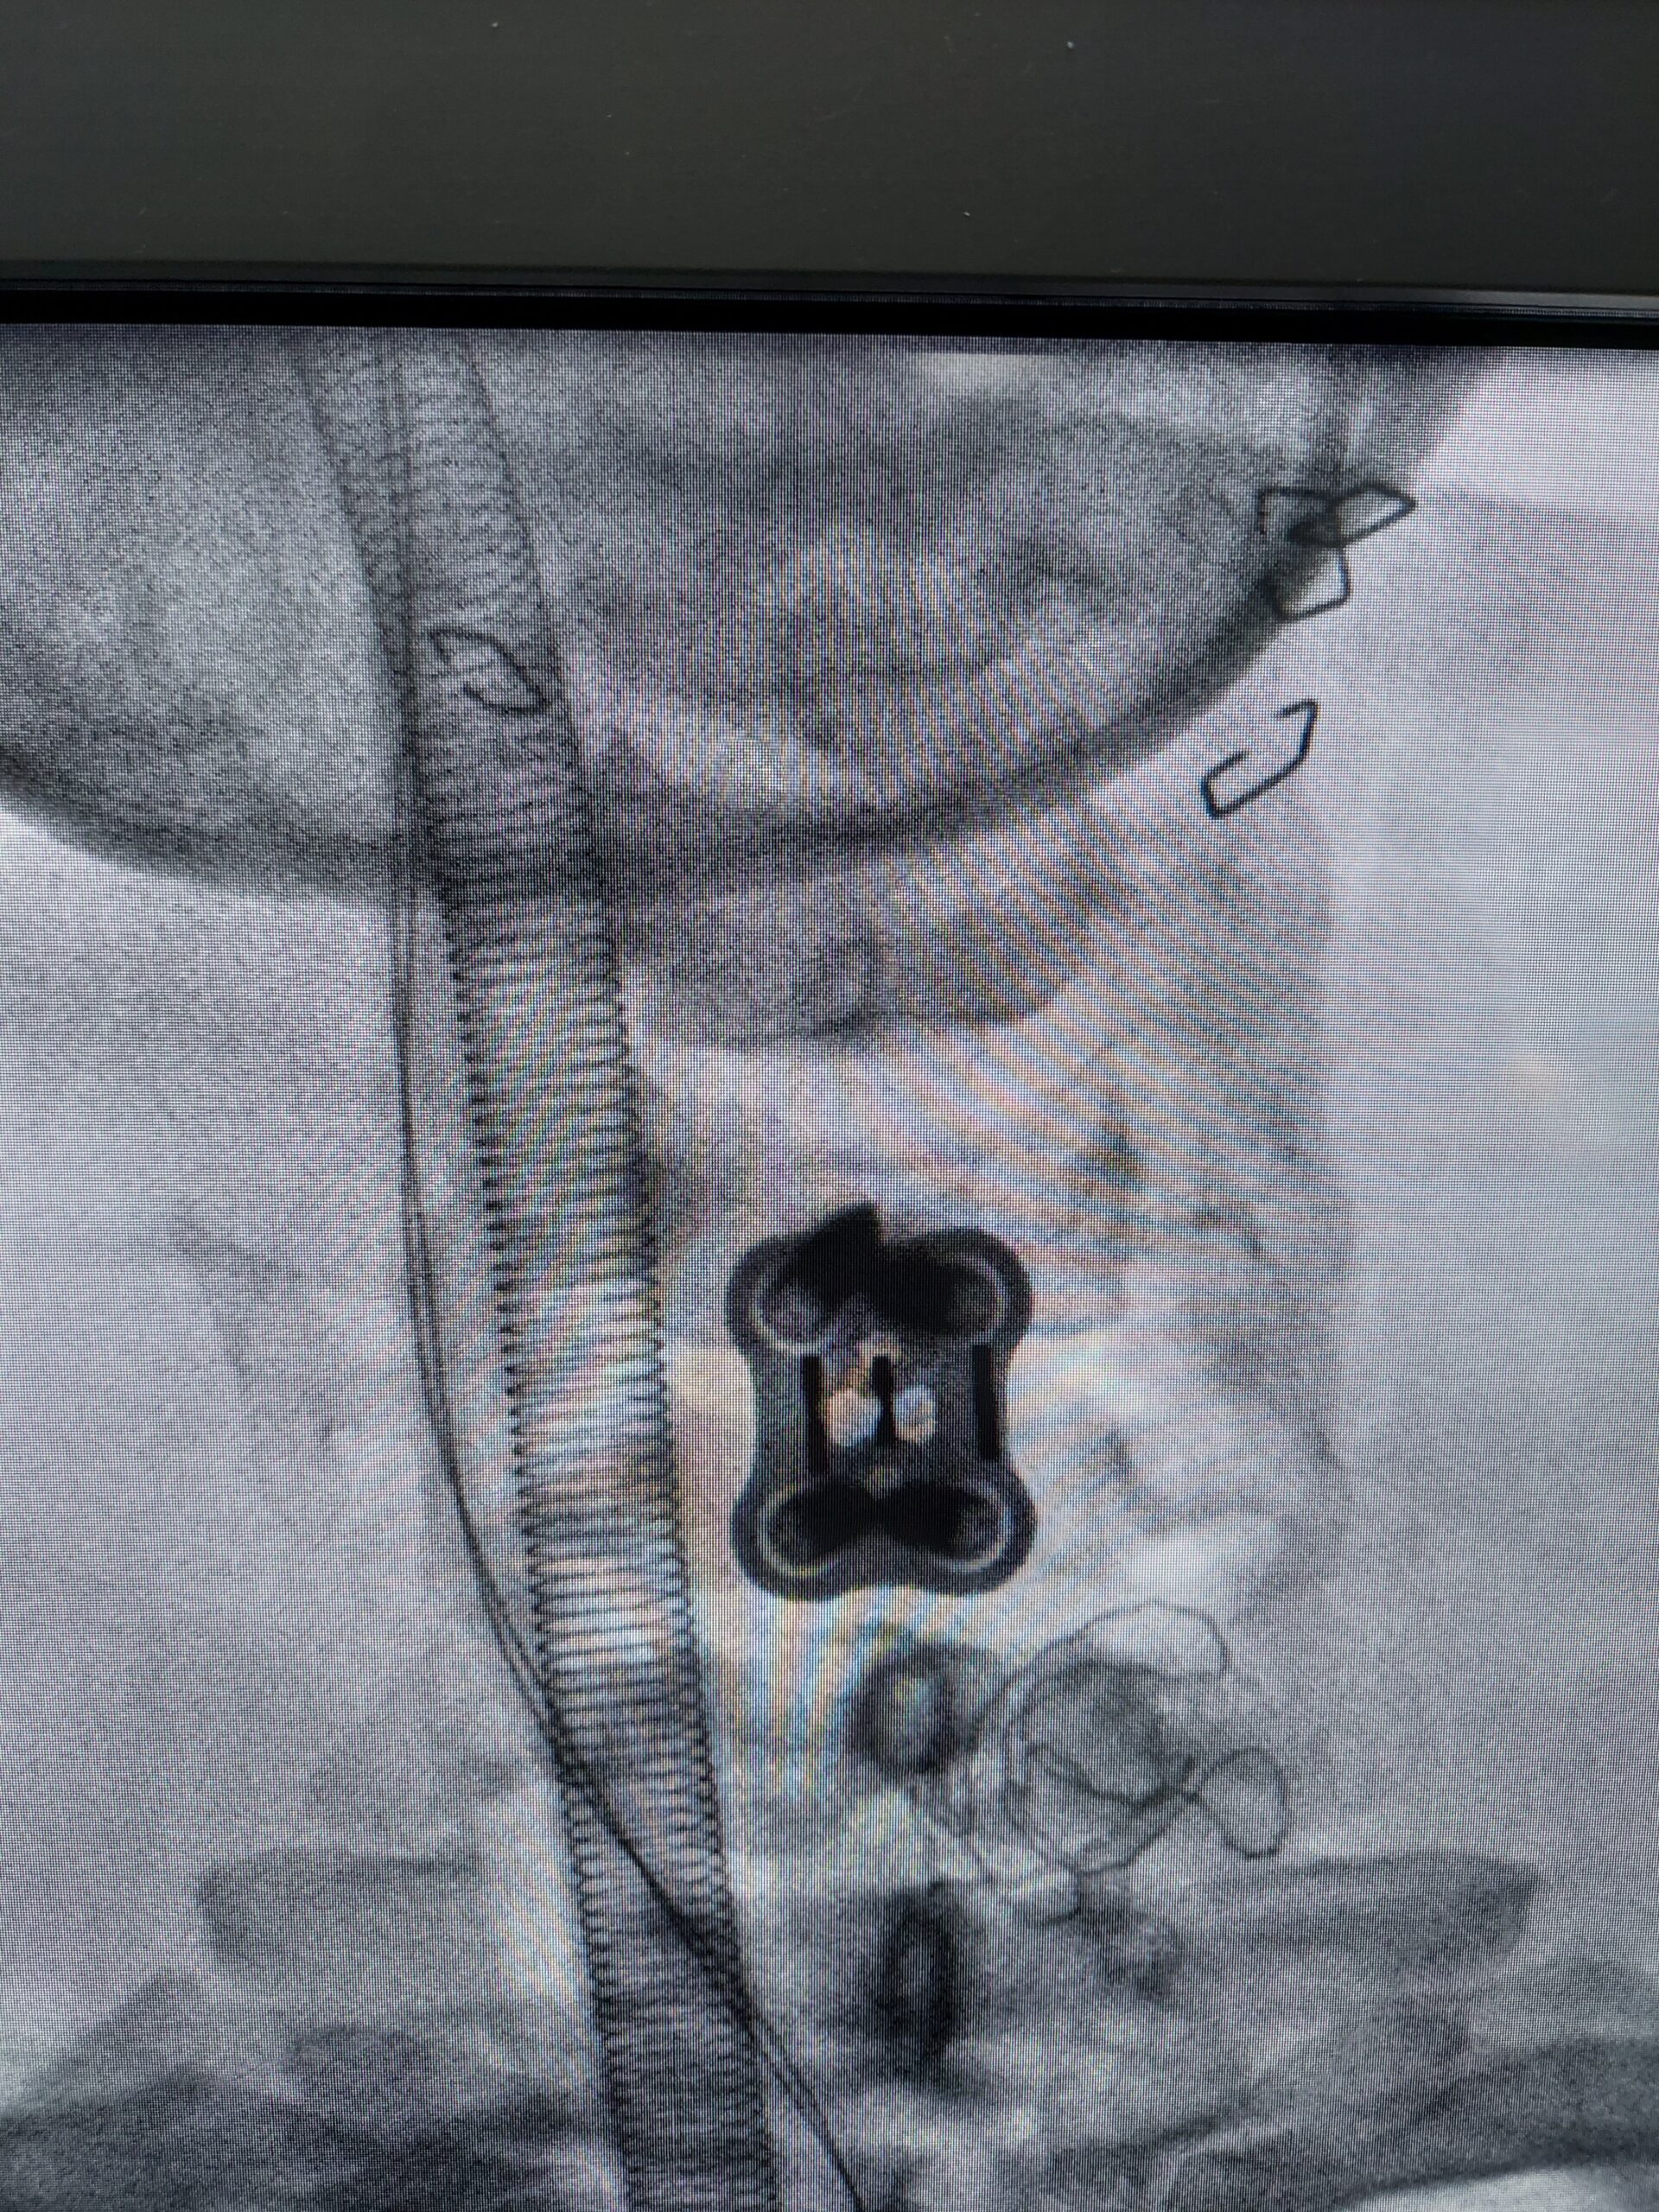

During the procedure, the affected disc or discs are removed from the front of the neck (anterior approach), and a bone graft and possibly a metal plate or cage are inserted to stabilize the spine and promote fusion between the adjacent vertebrae. ACDF may be performed at one or more levels of the cervical spine, depending on the location and severity of the spinal condition.

4. Bone Graft Placement: A bone graft, often taken from the patient’s own hip bone or a bone bank, is inserted into the empty disc space to promote fusion between the adjacent vertebrae.

5. Hardware Placement: Metal plates, screws, or cages may be used to stabilize the spine and facilitate fusion.